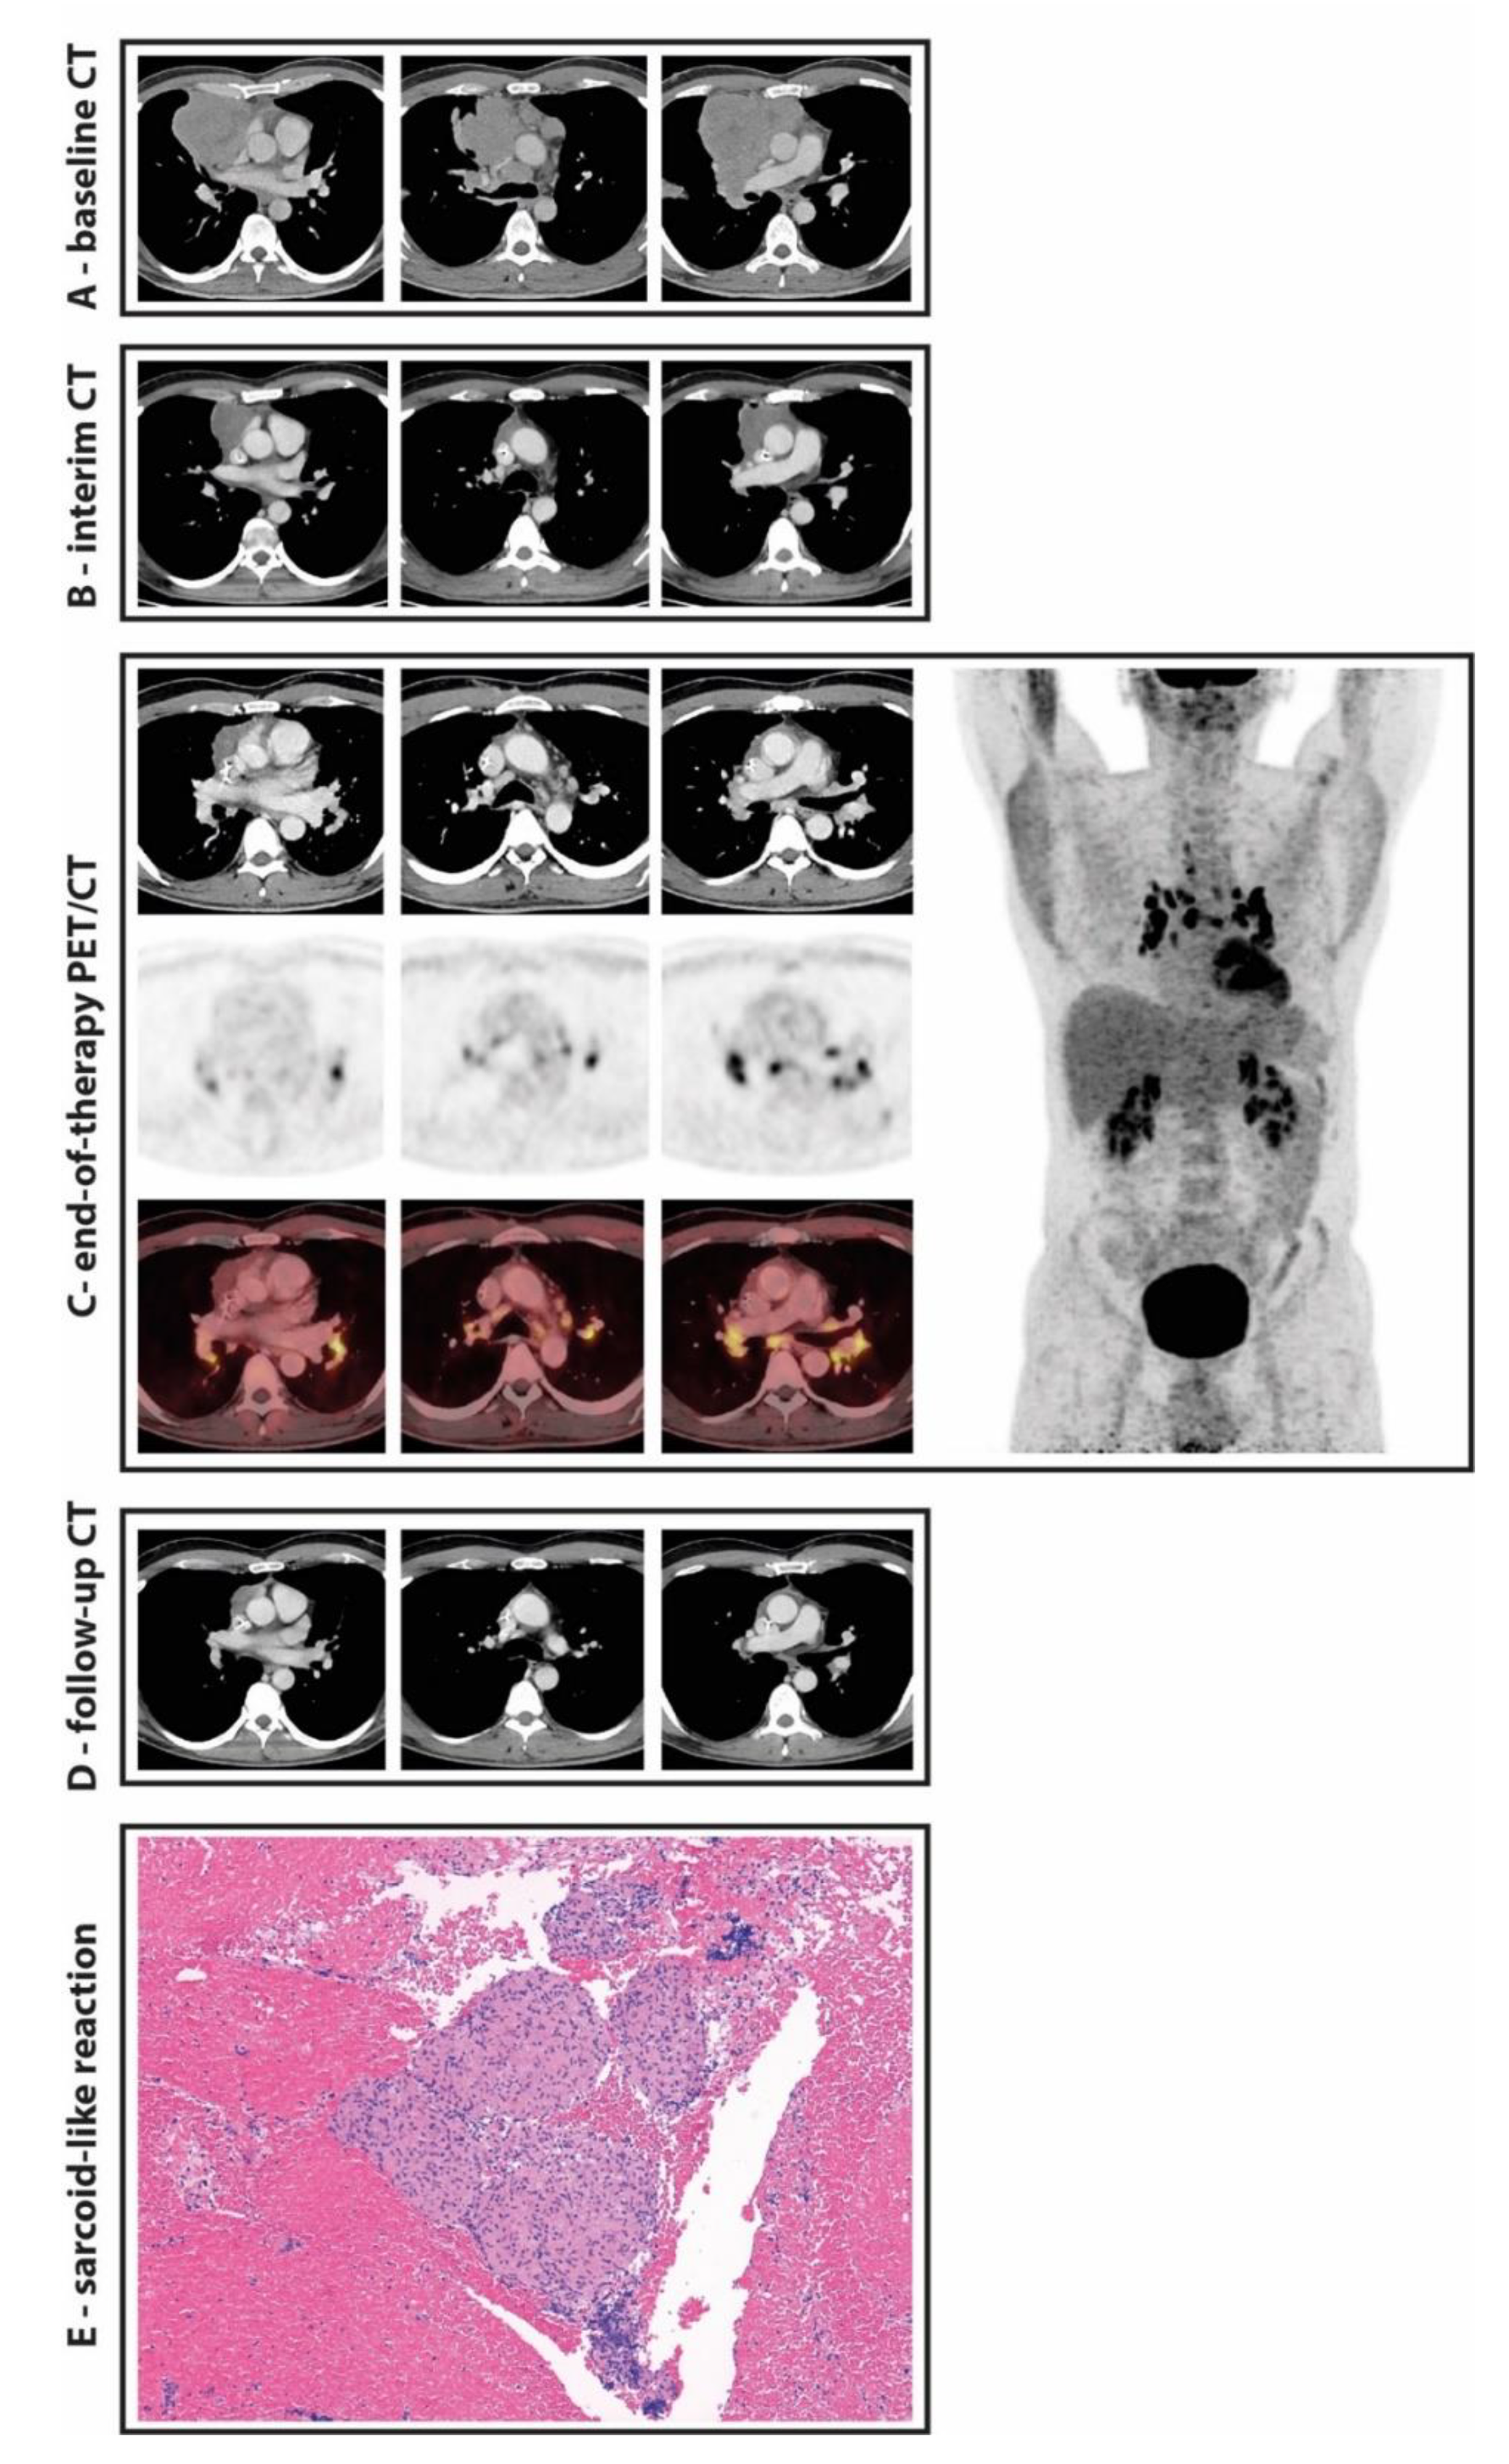

Sarcoid-Like Reaction in Non-Hodgkin’s Lymphoma—A Diagnostic Challenge for Deauville Scoring on 18F-FDG PET/CT Imaging

Winkelmann, M.; Rejeski, K.; Subklewe, M.; Ricke, J.; Unterrainer, M.; Rudelius, M.; Kunz, W.G. Sarcoid-Like Reaction in Non-Hodgkin’s Lymphoma—A Diagnostic Challenge for Deauville Scoring on 18F-FDG PET/CT Imaging. Diagnostics 2021, 11, 1009. https://doi.org/10.3390/diagnostics11061009